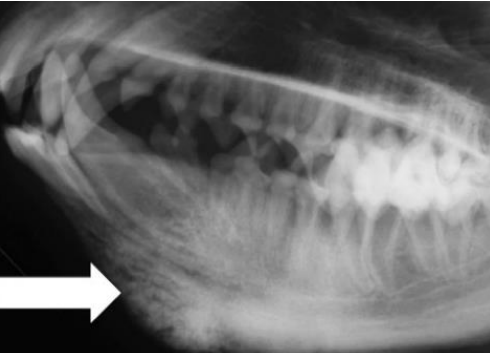

![]() ![]() | - caudal mandibles์ irrecular bone density๊ฐ ์ฆ๊ฐ. - tympanic bullae์ ๋ฐ๋๋ ์ฆ๊ฐ. - 1/3์ ํ์๋ mandible์ ๊ตญํ๋ ๋ณ๋ณ์ ๋ณด์ด์ง๋ง, ์ผ๋ถ ๊ฒฝ์ฐ skull์ ๋ฐ๋ฅ์ ๋ณ๋ณ, ๋๋ ๋๊ฐ๊ณจ ์์ฒด๊ฐ ๋น๋(thickened calvarium). - ๊ฐ๊ฐ ์ฑ์ํด ๊ฐ๋ฉด์, ์๋ก์ด ๋ผ์ ๊ฐ์ฅ์๋ฆฌ๊ฐ ๋งค๋๋ฌ์์ง๊ณ , ๋น์ ์ ๋ถ์๊ฐ ์ค์ด๋ฆ. |